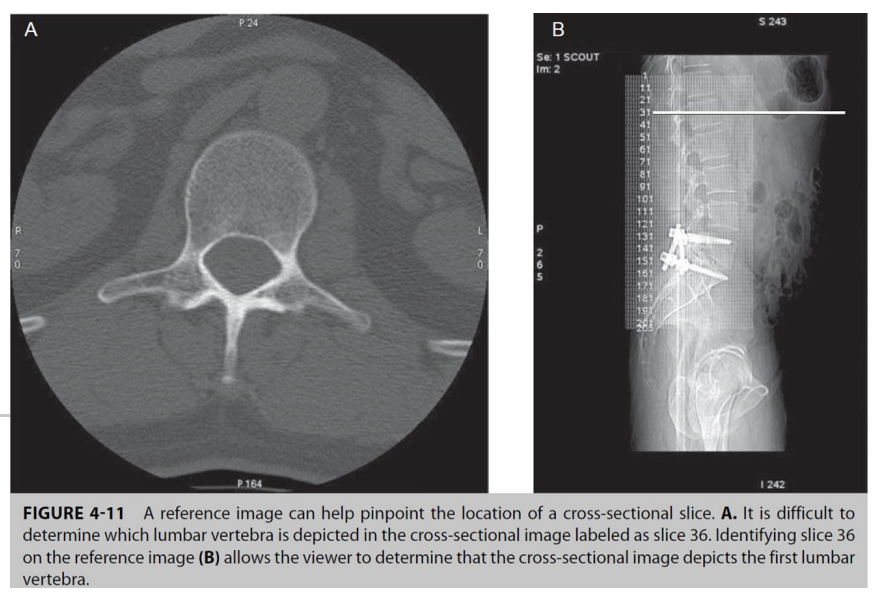

What is the reference image function

displays the location of slices through the slice lines in corresponding locations on the scout image

- feature aids in localizing slices